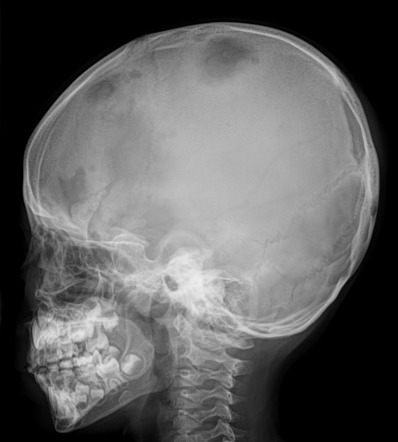

Hole within a hole appearance of skull is seen in _____, apart from langerhans cell histiocytosis